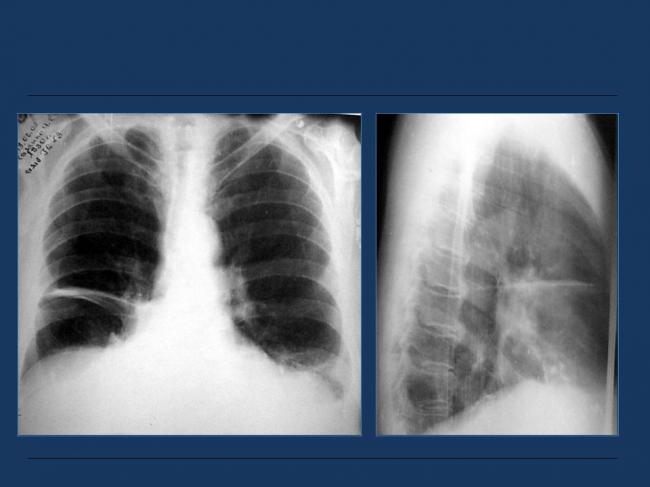

Помимо опроса и объективного осмотра, включающего перкуссию и аускультацию грудной клетки, проводят рентгенологическое исследование в двух положениях тела (в 2-х проекциях). Это основной метод обнаружения ателектазов легких.

На рентгеновских снимках выявляют следующие признаки, указывающие на спадение легочной ткани:

Однородное затемнение в области поражения. Размеры тени зависят от вида ателектаза: при долевом выявляется обширное затемнение, при сегментарном — в виде клина или треугольника, расположенного вершиной к корню легкого, дольковые ателектазы множественные и похожи на очаговую пневмонию. Дистензионный ателектаз расположен низко, около диафрагмы, имеет небольшие размеры и вид поперечных полос или темных дисков. Смещение органов: при компрессионном ателектазе смещение наблюдается в здоровую сторону, так как на стороне поражения давление больше, при обтурационном, наоборот – смещение будет в сторону ателектаза, так как на стороне поражения нарастает притягивающее отрицательное давление. Подъем купола диафрагмы – это видно по расположению печени.

Помимо всего перечисленного выше, рентгеноскопия, то есть исследование «вживую», позволяет увидеть куда смещаются органы в зависимости от фазы дыхания, кашля. Это является дополнительным признаком ателектаза, помогающим выявить тип болезни.

Предварительным, рентгенологическим диагнозом является «синдром правой доли», при котором выявляется затемнение площади средней доли правого легкого.

Частое возникновение ателектаза правого легкого связано с анатомическими особенностями правого среднедолевого бронха: он узкий и длинный, поэтому часто происходит его перекрытие при патологическом процессе.